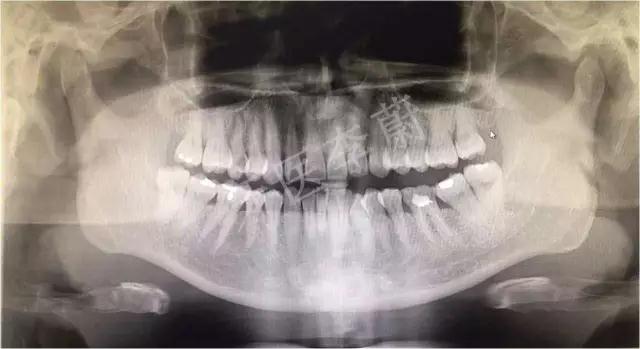

X片示:15残冠影,根尖有骨密度降低影。

曲面断层片